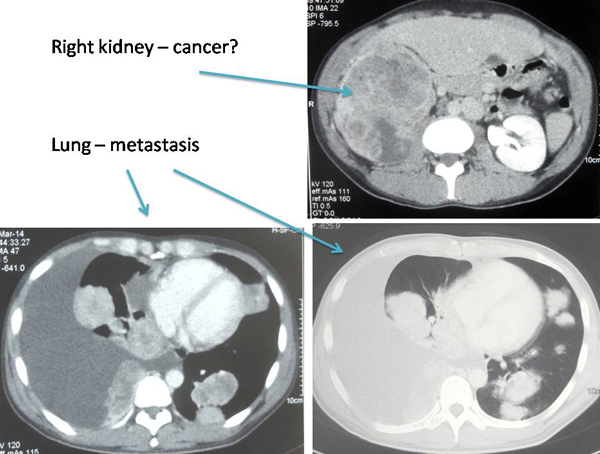

LKF (E324) is a 32-year-old male. Sometime in June 2013, he passed out blood in his urine. USG of the abdomen showed a large right renal mass suspicious of renal cell carcinoma. He was asked to go for CT scan but decline due to financial constraint. In early 2014, he started to cough, sometimes with blood stain sputum. He had shortness of breath, chest pain and hoarse voice. LKF was referred to the respiratory unit of the general hospital. CT showed metastatic lung cancer, the primary was probably from the kidney. Because of right pleural effusion, pleural tapping was done. Bronchoscopy and biopsy were performed and confirmed cancer. LKF was subsequently referred to the oncology and urology units for further management. He was told that he might have to undergo chemotherapy (expensive drug which he could not afford) and later an operation to remove his cancerous, right kidney.

I explained to LKF and his sisters that this is a Stage 4 cancer and I would try to best to help, but don’t expect magic from us. LKF was prescribed herbs: Capsule A, C and D and herbal teas: Kidney, Lung 1 & 2, Lung Phlegm, deTOX + WF.